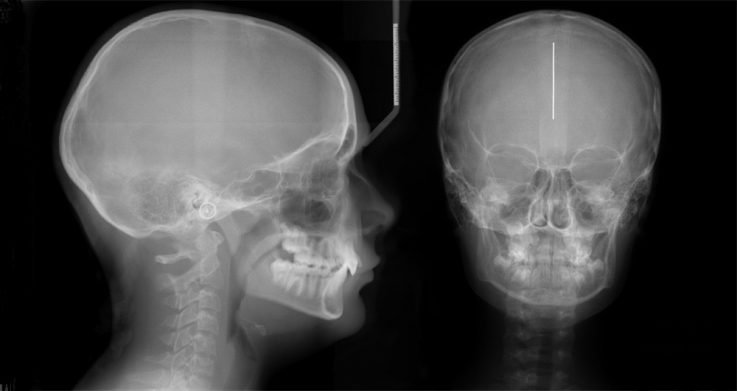

Однако точное определение заболевания возможно только после изучения рентгеновских данных. Пациенту проводят процедуру рентгенографии, и если присутствует гайморит, область между глазами и верхней челюстью будет иметь непрозрачный, белый оттенок.

Если в пазухах нет патологии, то на рентгене костные стенки будут иметь четкие контуры.

При проведении рентгенографии гайморита можно заметить чёткий контраст между чёрными пазухами и белым инфильтратом, что часто называют симптомом «молока в стакане». Если рентгенолог видит этот симптом в двух проекциях, то диагноз гайморита подтверждается. При гнойном гайморите также наблюдается чёткое затемнение области гайморовых пазух при проведении исследования в боковой и прямой проекциях.

Обычно врач в первую очередь обращает внимание на носовые синусы. При нормальном состоянии они не заполнены воздухом, поэтому рентгеновский снимок покажет изображение в виде темных полуовальных образований по обе стороны носовой полости.

Если в полости носа есть жидкость, то на рентгенограмме будет видно затемнение. Врач может привести примеры рентгенограмм, чтобы проиллюстрировать этот факт. Он объясняет, что выявление гайморовых пазух не зависит от уровня или типа затемнения на снимке. Наличие затемнения не всегда означает наличие гайморита. Точно так же нельзя сразу определить наличие фронтита. Гайморит представляет собой воспалительное заболевание пазух носа, в которых может накапливаться различного вида жидкость.

При этом заболевании на рентгеновском снимке можно увидеть черные области в пазухах, содержащие светлое инфильтративное вещество. Врач может определить наличие патологии по резкому контрасту на снимке и отличить её от нормального состояния. Важно помнить, что подобное изображение на рентгене не всегда указывает на наличие заболевания. Поэтому не следует заниматься самолечением, а сразу же обратиться к отоларингологу для консультации. После установления диагноза гайморита врач назначит соответствующее лечение.

Накопление гнойного материала в синусах при гайморите можно увидеть на изображении как светлое пятно на фоне темной полости. При значительном объеме содержимого можно разглядеть его горизонтальную линию.

Иллюстрация здоровых пазух напоминает темные полуовальные полости, расположенные по обе стороны от носа. Они имеют одинаковую окраску и соответствуют глазницам. Это свидетельствует об отсутствии любых патологий. Появление даже маленьких светлых областей будет указывать на начало воспалительных процессов. Чем сильнее воспаление, тем ярче белые пятна. Кроме того, изображение носовых пазух изменится. При гайморите на рентгеновском снимке пазухи носа будут иметь неровные контуры и утолщенные стенки.

При осуществлении диагностики врач проводит осмотр и оценку состояния решетчатой кости. Гайморит способен вызвать распространение воспаления в верхнечелюстные гайморовы пазухи. В них может накапливаться жидкость различного типа: катаральная, слизистая или гнойная. На рентгеновском снимке она будет заметна как светлое пятно с четкими контурами на фоне темной носовой пазухи.